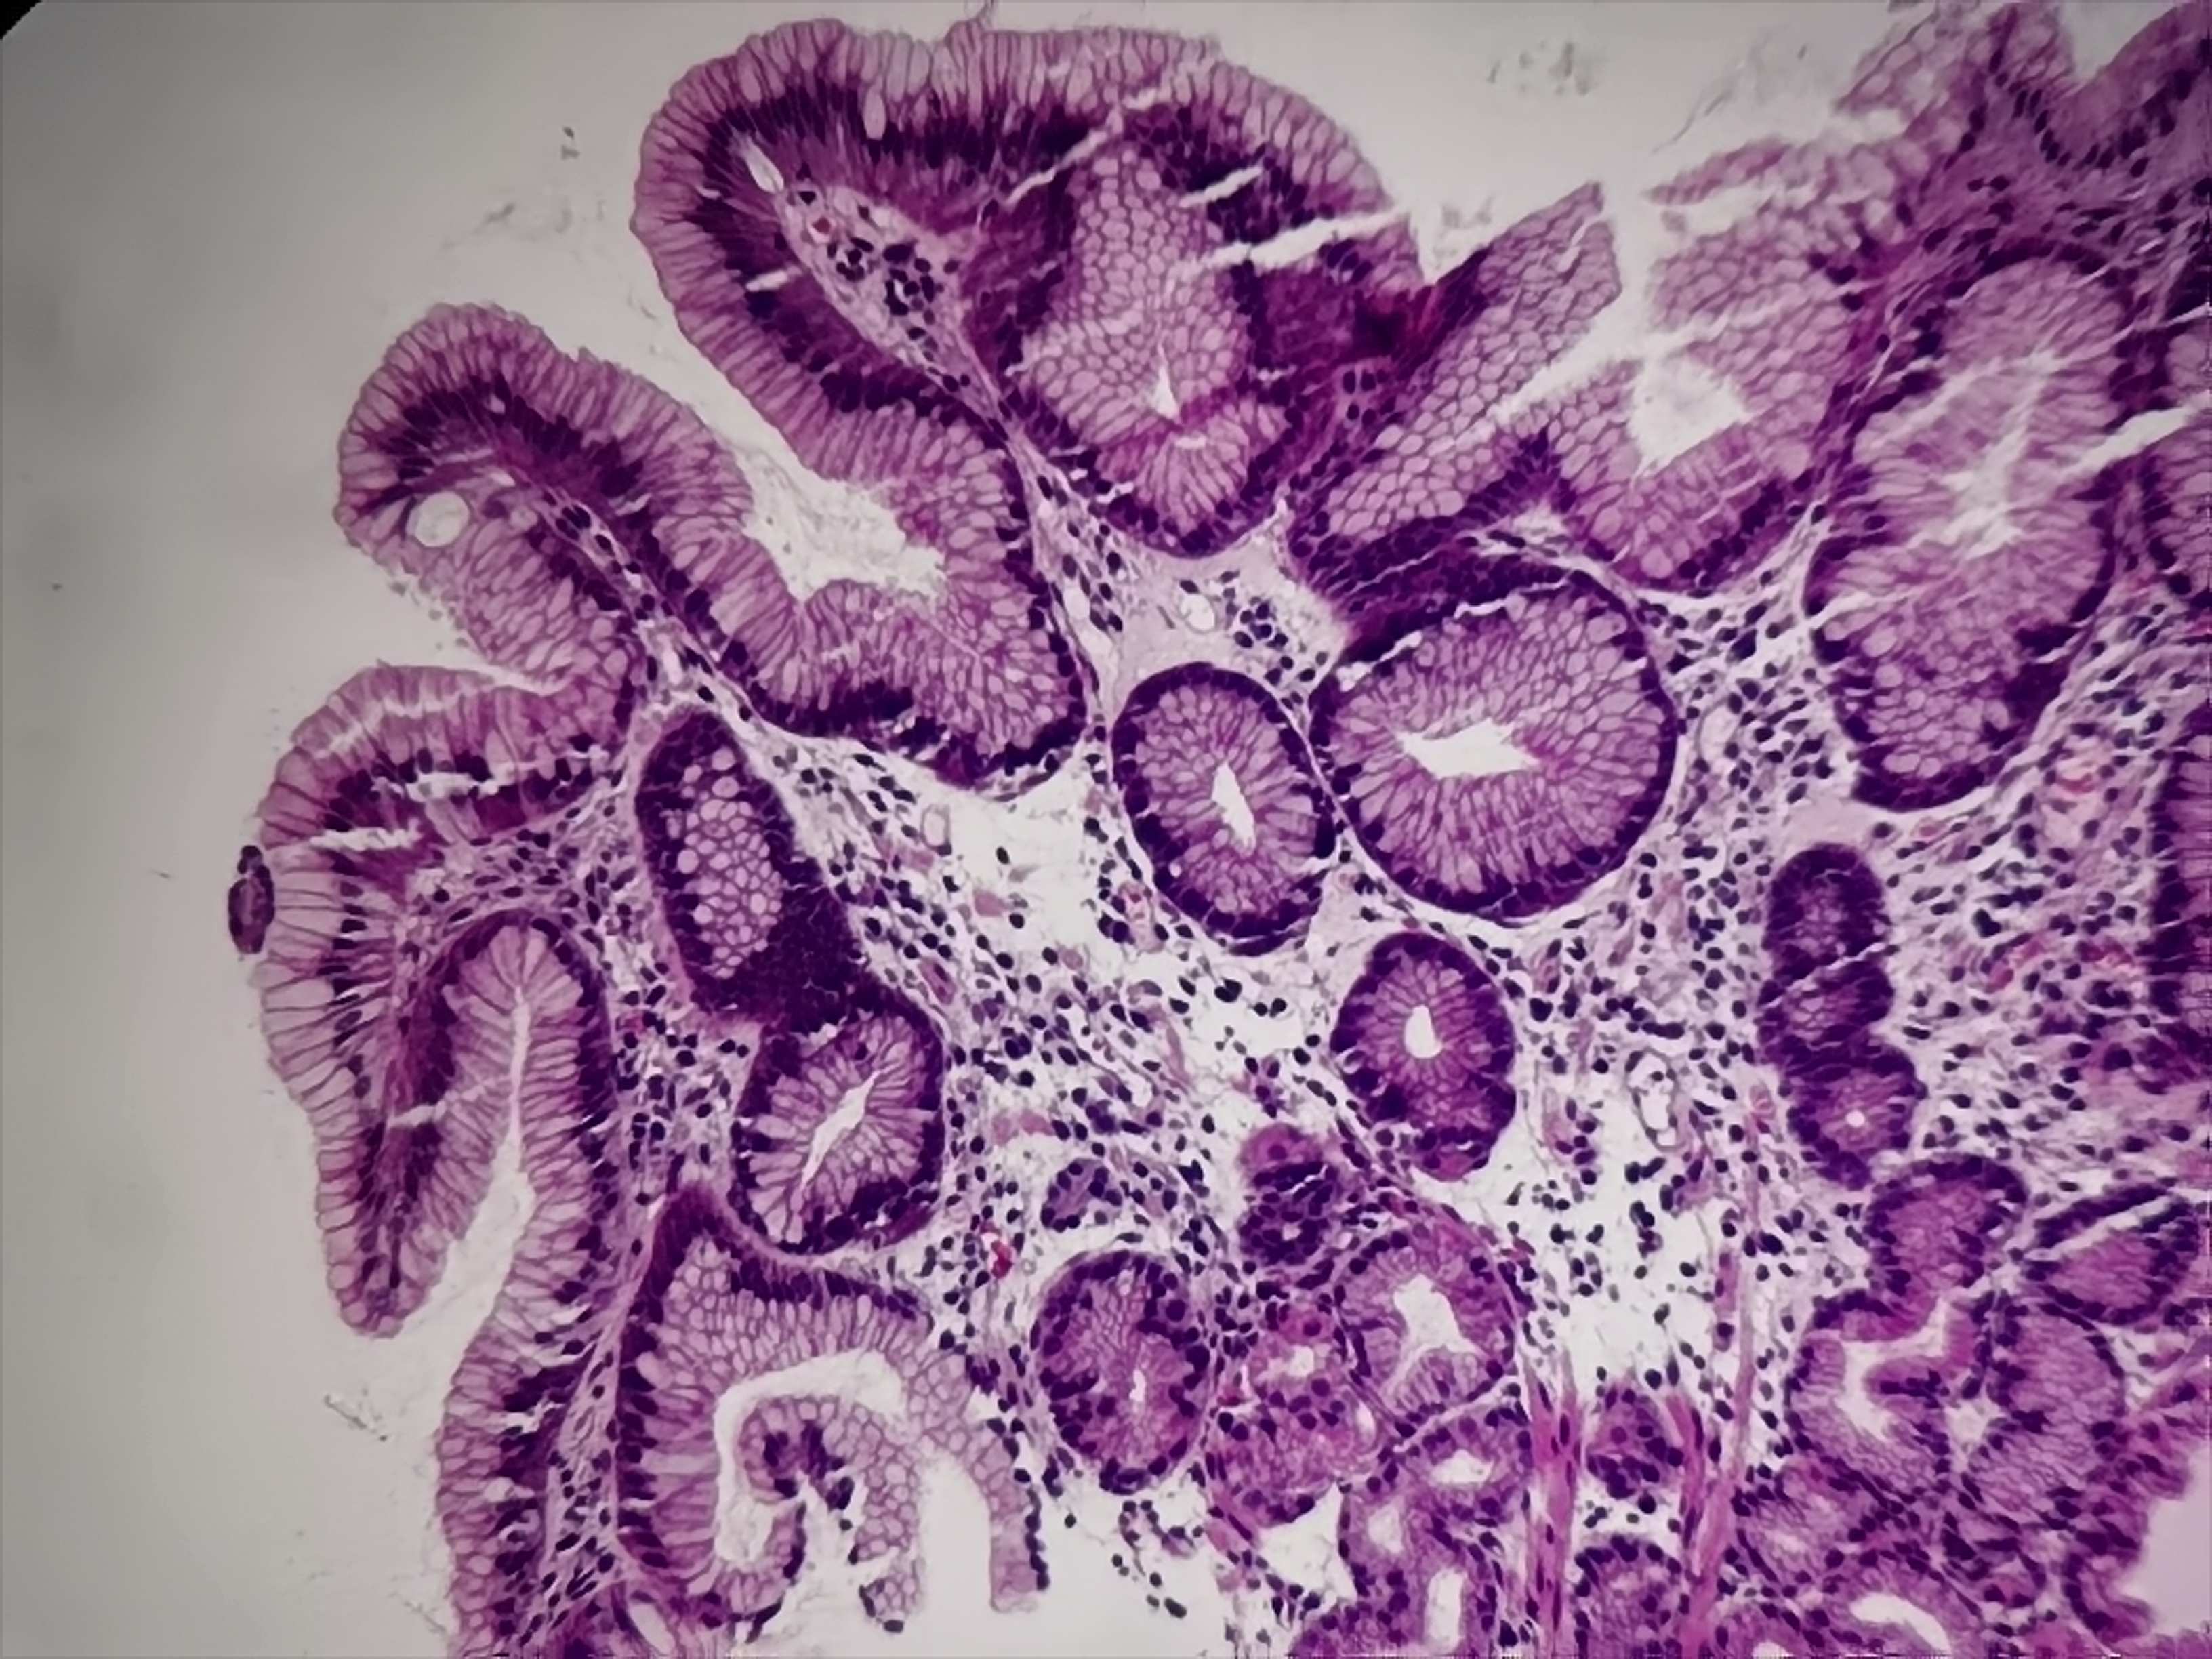

胃体活检

性别

男

年龄

57岁

临床诊断

胃多发溃疡

一般病史

胃体可见多枚点状溃疡

标本名称

胃体粘膜活检

大体所见

灰白灰红组织2块

图1

符合溃疡,HP?